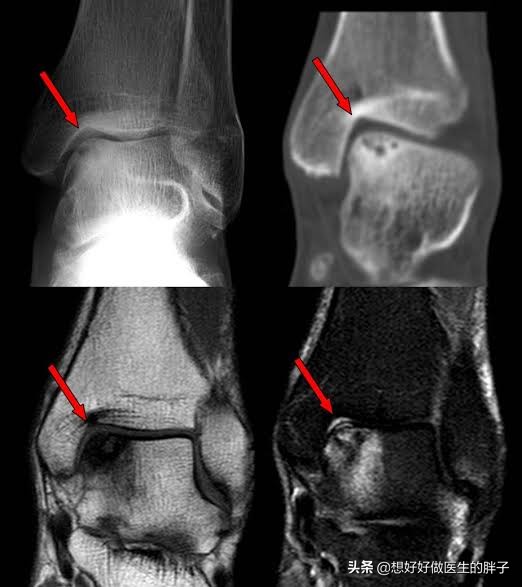

踝关节的软骨损伤

其实踝关节的损伤,最讨厌的还是踝关节软骨的损伤,因为软骨一旦损伤之后,就有可能导致创伤性的关节炎,患者将会面临长时间的关节疼痛和日益加重的关节变形。

通常情况下踝关节的损伤比较容易导致软骨的损伤,因为踝关节周边肌肉力量并不是特别强,虽然有的时候扭伤并不会造成骨折,但是一个过度的撞击就有可能损伤到关节腔的软骨。

这种情况通常要进行踝关节核磁检查,明确关节腔软骨是否存在退变,因为在普通x线上,我们看不见关节软骨。

如果明确了存在关节软骨的损伤,早期我们可以通过控制体重、加强踝关节功能的康复锻炼,可以尝试关节内注射玻璃酸钠或者是prp帮助促进损伤的修复,观察能否帮助患者缓解症状。如果疼痛比较明显,可以考虑进行关节镜手术,观察能否帮助患者减轻症状。三个月的时间个人倾向认为还是以保守治疗为主,暂时可以不用手术。